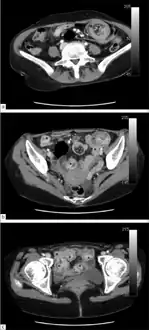

Axial CT scans of the abdomen showing multiple intussusceptions in the jejunum -

Small intestinal invagination on computed tomography -